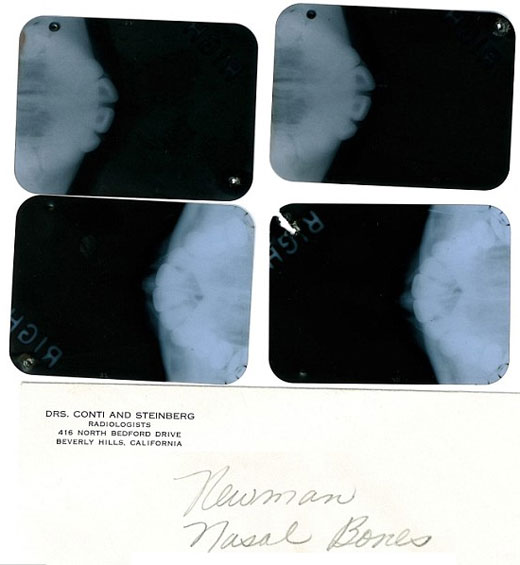

A las reveladoras notas escritas por el médico Michael Gurdin, supuestamente encargado de llevar a cabo la operación quirúrgica en 1950, se suman varias pruebas de rayos X realizadas el 7 de junio de 1962, dos meses antes del fallecimiento de la artista, en las que se pueden apreciar desde diferentes ángulos los huesos faciales de Marilyn, sus conductos nasales y su paladar.

Radiografías de Marilyn Monroe, bajo el nombre de Marilyn DiMaggio, sacadas por un joven médico en 1954.